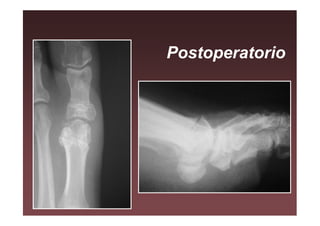

Postoperatorio